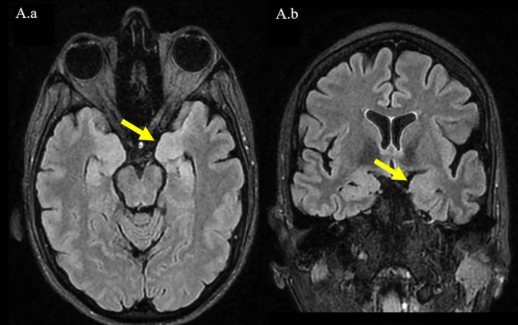

🤵♀️A 41-year-old woman develops progressive dysphagia, diplopia, and limb weakness. Days later she deteriorates with seizures and decreased consciousness. Brain MRI is performed during ICU admission. 🥼What is the most likely diagnosis?